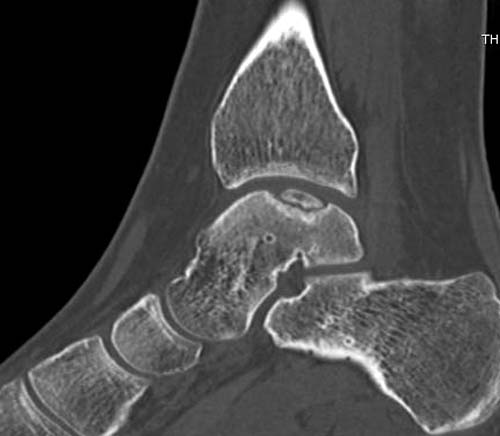

Разбираемый случай не имеет ничего общего с классическим Аваскулярным Некрозом Таранной кости. Здесь так назывемый (osteochondral defect) или osteochondritis dissecans (OCD) таранной кости, при котором патология локализуется в медиально-верхнем нагрузочном отделе. В основном OCD

встречается после хронической травмы, но бывают случаи врожденного генеза, которые обнаруживаются при случайных исследованиях.

на рентгенограммах не всегда заметны склерозные участки, и поэтому в большинстве диагноз устанавливается поздно. Приход КТ и МРТ улучшил диагностику, и в срезах внутри кисты можно увидеть жидкость, но это не означает проявление симптоматологии. Симптомы проявляются с момента образования внутрисуставных краевых фрагментаций!

При умеренных проявлениях можно ограничиться консервативным лечением, но при выраженной симптоматике необходимо удалить свободные фрагменты.

Артроскопия с дебридментом приносит облегчение, но огромные медиально-верхние дефекты надо замещать. Хирургический доступ через медиальную лодыжку, а для замещения применяют современные алломатериалы.